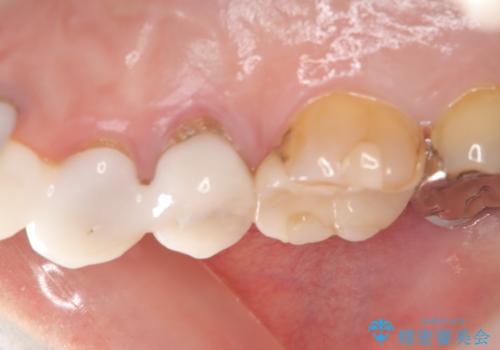

- 右上の歯に異和感があるとの事で来院した患者様です。

検査の結果、歯根破折が認められたため、抜歯即時インプラント(1DAYインプラント)を行いました。